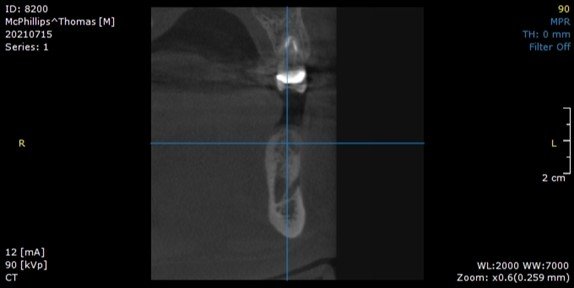

It can be seen on the CBCT image that there is a loss of bone starting at the middle of the implant to the apex. The implant was not mobile, and a perio probe did not penetrate through the sulcus, indicating that bone was present around the occlusal half of the implant.